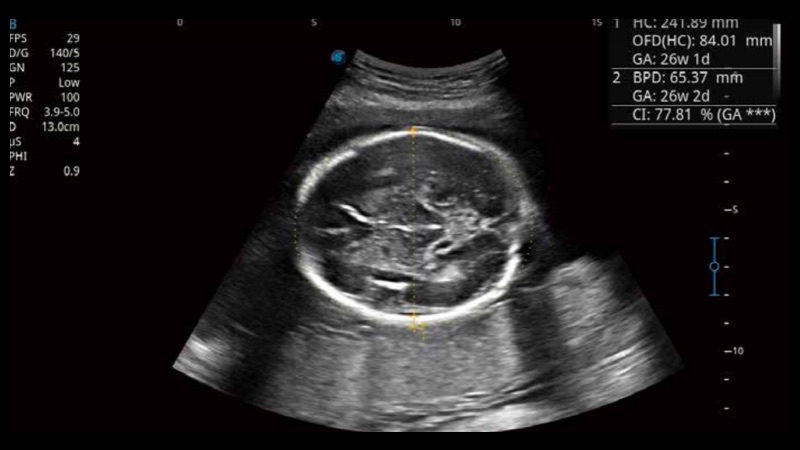

S-Fetus基于大數(shù)據(jù)深度學(xué)習(xí)算法,能夠幫助您在產(chǎn)前篩查過程中智能識(shí)別胎兒標(biāo)準(zhǔn)切面、自動(dòng)測(cè)量并錄入報(bào)告。一個(gè)按鍵,即可智能、精準(zhǔn)、高效地獲取胎兒生理指標(biāo),極大簡(jiǎn)化您的產(chǎn)科檢查操作。

可快速對(duì)產(chǎn)科掃查切面完成胎兒生理學(xué)參數(shù)的自動(dòng)測(cè)量,減少操作者按鍵次數(shù),大幅提升檢查效率。